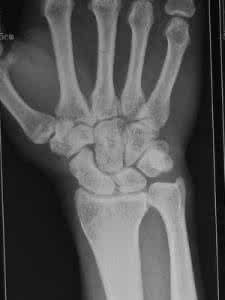

因外伤引起者为外伤性脱位;因关节病变引起者为病理性脱位;脱位后,关节面完全丧失对合关系者为完全脱位;部分丧失者为半脱位。外伤性脱位较多见,且多发生在青壮年。最易发生脱位的关节是肘关节,其次是肩及髋关节。伤后关节局部疼痛、肿胀、活动障碍及出现畸形,多可据此作出诊断。为了确定脱位的方向、程度及是否合并骨折,X线检查是必要的。对脱臼者应及时进行手法复位,越早越好。复位后应使关节固定于稳定位置2~4周;解除固定后还应进行主动的功能锻炼,以利恢复关节功能。如果手法复位失败,应行手术切开复位。

肩关节脱位时常常有合并症发生,肩关节有脱位病例约30~40%合并大结节骨折,也可发生肱骨外科颈骨折,或肱骨头压缩骨折,有时合并关节囊或肩胛盂缘自前面附着处撕脱,愈合不佳可引起习惯性脱位,肱二头肌长头肌腱可向后滑脱,造成关节复位障碍,腋神经或臂丛神经内侧束可被肱骨头压迫或牵拉,引起神经功能障碍,也可以损伤腋动脉。